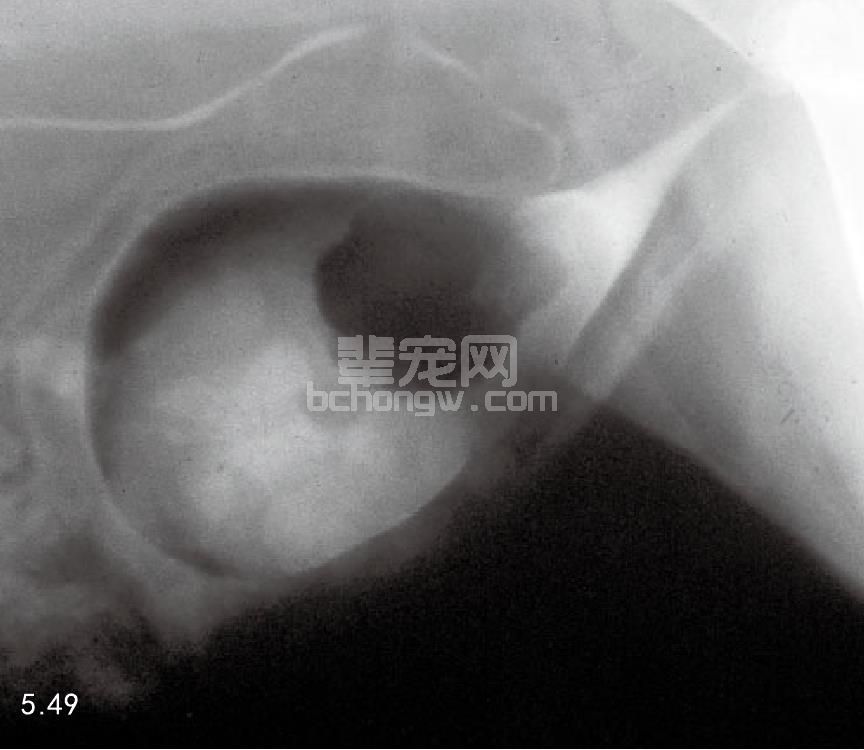

诊断 尿液分析对尿液沉积物做细胞学检查时很难发现肿瘤细胞,用生理盐水冲洗膀胱做细胞检查更可靠。 直接的组织抽吸也能获得准确的细胞学检查结果(图5.48)。X线片通常没有太大的价值,但是造影检查包括双 重造影和逆行性尿道造影可以显示充盈性缺陷,这些缺陷出现在正常光滑的造影剂药物膜的表面(图5.49~图 5.52)。超声在细针抽吸体内液体的帮助下也有助于诊断(图5.53)。

图5.49和图5.50 犬移行性细胞癌的膀胱双重造影:肿瘤为充盈缺失部分,图5.49为侧位片;图5.50为腹背位片。